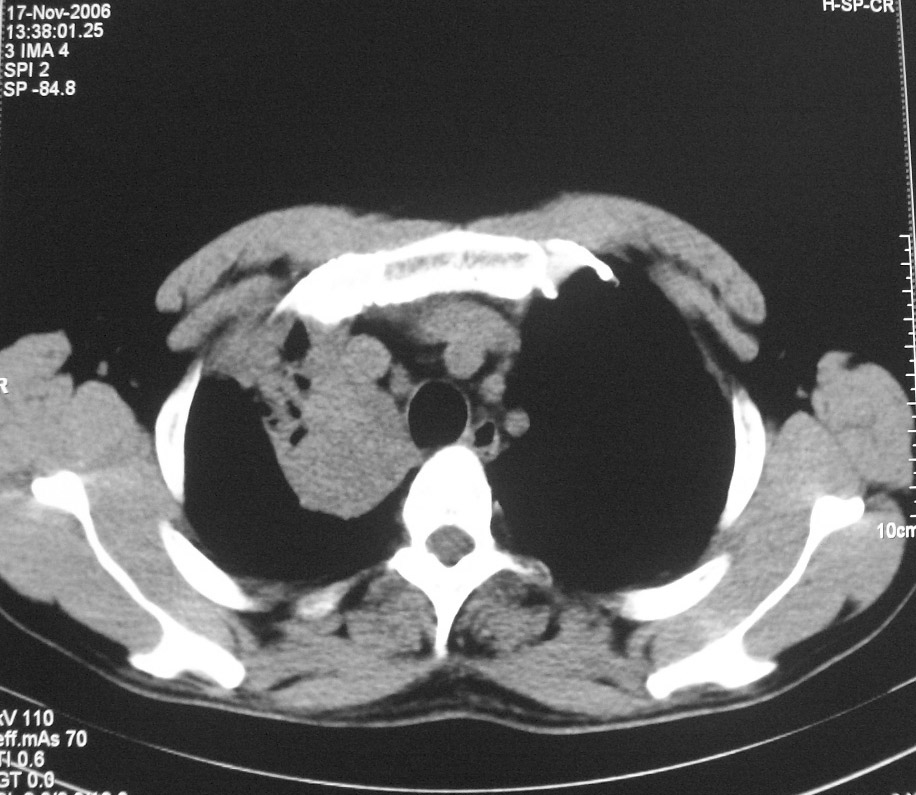

标题: CT5485:[原创]肺部占位请讨论

右肺上叶中央型肺癌并上叶肺不张、纵隔淋巴结肿大

右上叶支气管后壁明显增厚,支持右肺上叶中央型肺癌伴右上叶肺不张、纵隔淋巴结肿大。

右上叶支气管开口变窄,纵隔见肿大的淋巴结。支持右上叶中心型肺癌并右上叶不张纵隔淋巴结肿大。

右肺上叶中央型肺癌并上叶肺不张、纵隔淋巴结肿大.右侧少量胸腔积液。

右上肺中心型肺癌并肺不张,纵膈淋巴结肿大。右侧少量胸腔积液。